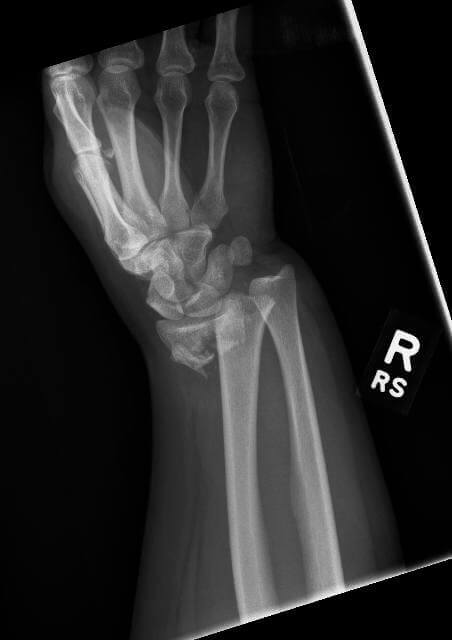

Pe data de 10 ian 2015 am suferit o fractura epifiza distala radius stang cu minima deplasare. în căderile pe mână ca cele din imagine se pot produce fracturi ale extremităţii distale a unuia sau a ambelor oase ce alcătuiesc antebraţul. Sfat fractura epifiza distala radius cu deplasare secțiunea. Buna seara in data de 23 august am cazut cu skateboardul si in urma unei radiografii mi s a spus ca am fisura la incheietura mainii drepte dar o doamna de la ortopedie mi a dat verdictul ca as avea fisura pe data de 8 septembrie am scos gipsu incheietura este desumflata doar.

Aceasta regula se aplica si in cazul fracturilor de epifiza distala radius partea inferioara a antebratului. In urma cu o saptamana mi am fracturat incheietura mainii drepte dupa ce am cazut pe mana in timpul unei activitati sportive dupa aprox. Mecanism de producere este un traumatism prin cadere cu mana in extensie cel mai frecvent sau in flexie. Fragmentele osoase rupte trebuie repozitionate corect si fixate corespunzator pentru a preveni miscarea lor ulterioara pana ce fractura se vindeca consolideaza.

Fractura de epifiză distală de radius. Pe data de 9 feb se indeparteaza aparatul gipsat. Mi s au facut radiografii dupa care a urmat tractiunea si imobilizarea in atela gipsata in v cu care am stat doua saptamani. Afla mai multe informatii in acest articol.